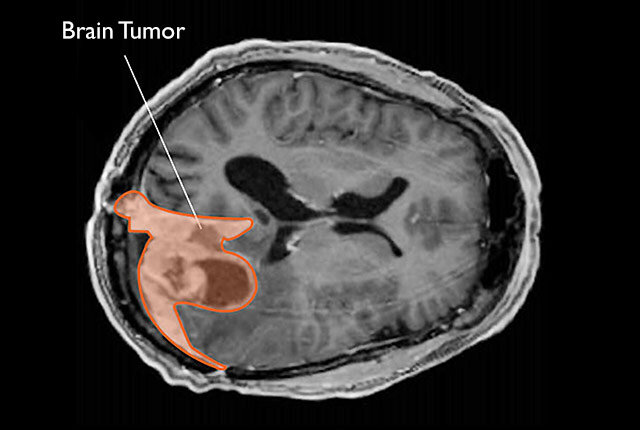

Participants’ substance use habits were tracked, with self-reports detailing the initiation of substances such as alcohol, nicotine, cannabis, and other drugs. Each child underwent magnetic resonance imaging (MRI) scans to evaluate their brain structures. Using these images, researchers analyzed 297 distinct brain-related factors, including the overall volume of the brain, cortical and subcortical volumes, thickness of the cortex, surface area, and sulcal depth—all of which help paint a picture of the brain’s anatomy. Numerous factors were considered in the study, including age, sex, pubertal status, family influences, prenatal exposure to substances, and the specific MRI scanners used during the study.

What the researchers found was both fascinating and insightful. The study revealed that certain structural brain differences, which were apparent even before the children had started using substances, could be considered potential risk factors for early initiation. These brain differences included larger overall brain volumes, thinner regions of the prefrontal cortex, and greater volumes in specific brain areas, such as the hippocampus and globus pallidus. These differences were particularly noticeable in regions known to be involved in decision-making, impulse control, and reward processing—areas that are directly relevant to the likelihood of making risky decisions like experimenting with drugs or alcohol.

Specifically, the study found significant associations between substance use initiation and cortical thinning in the prefrontal cortex, particularly in the rostral middle frontal gyrus. Interestingly, regions associated with sensory processing, including areas in the occipital, parietal, and temporal lobes, displayed an increase in cortical thickness among children who later went on to use substances. Larger volumes were noted in the hippocampus and globus pallidus in children who would eventually engage in substance use, although cannabis use was particularly linked to reduced right caudate volume.